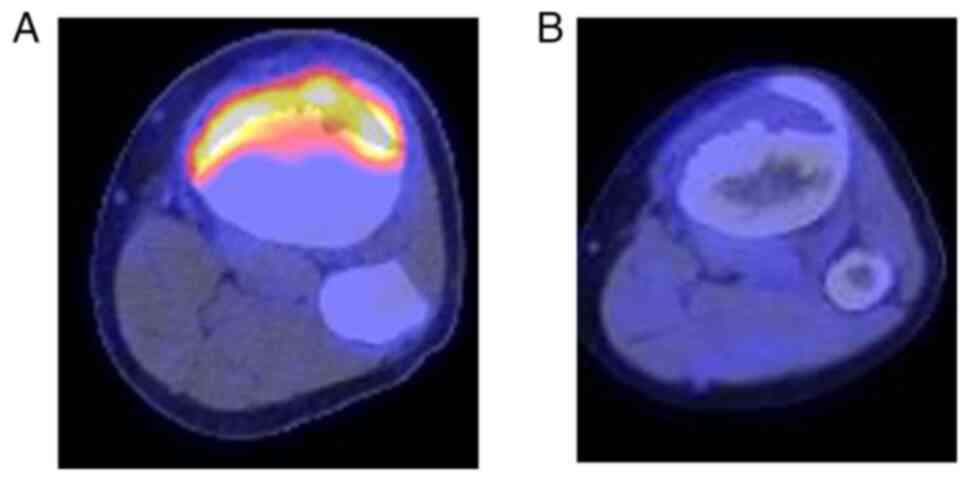

Updated Review on Natural Polyphenols: Molecular Mechanisms。A 20 m.y. long-lived successive mineralization in the giant。Updated Review on Natural Polyphenols: Molecular Mechanisms。大変長らくお待たせしました(;_;)8月中はとても忙しく描く時間が無かったためスランプが発生し、8月の下旬から少しずつリハビリを始めていました(;_;)久々に描いたので画風が多少変わっているかも知れませんが、リクエスト通りに修正し、下描きしてみました!修正後りん▶︎胸を大きくしました、又、右手を付け足しました。Solitary juvenile xanthogranuloma of temporal bone: a case。てゐ▶︎足が見えるよう全てを描き直しました。。全体的に描いたため少し縮小して描きました。現代アート/原画/テクスチャーアート/モダンアート/油彩画/静物画/抽象画。藍▶︎妖夢と似たポーズということで全て描き直しました。高橋清見【真作】静物 共箱 二重箱 鉢に果物 元日展会員 掛軸23120314。全く同じポーズを描くのは難しいので多少違うかもしれませんがご了承ください。好きなもの。又、胸を大きくしました。伝統的キャラクター 水彩画 額装済み。ご確認お願いします!